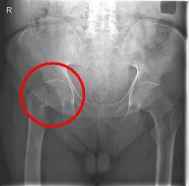

Oberschenkel 3

Picture: This picture shows the treatment of a severely displaced fracture with a so-called duo head prosthesis. The acetabulum was left here.

In older age and with stronger displacement of the fracture can be done by a duo-head prosthesis. Here only the femoral head is replaced, the hip socket is preserved. In case of simultaneous hip arthrosis, a total endoprosthesis (hip replacement) with replacement of the acetabular cup can be used.